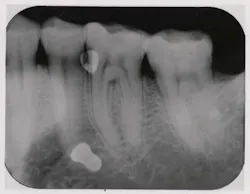

Fig. 1: Preoperative radiograph showing remaining endodontically treated roots.